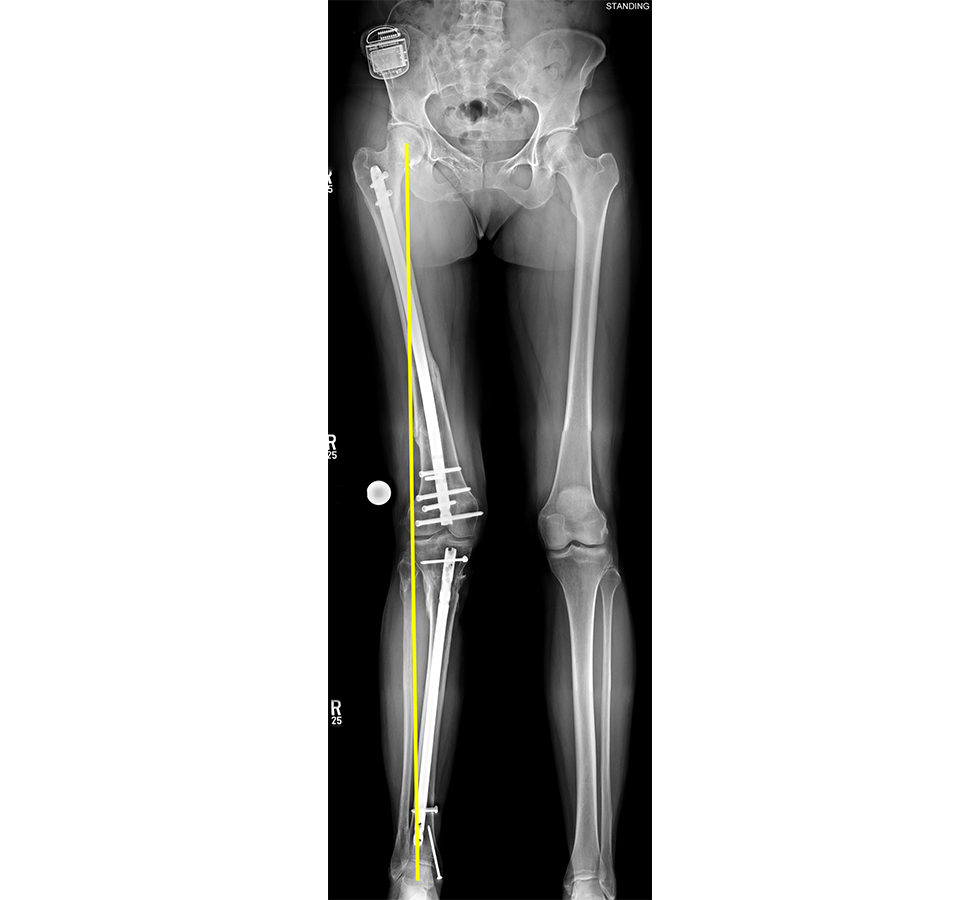

(Case provided by J. Spence Reid, Penn State Health Milton S. Hershey Medical Center, Pennsylvania, USA.)

- 47-year-old woman s/p separate femur and tibia trauma

- Valgus knee with external rotation through femur

- Deformity analysis revealed that the angular deformity was coming from her proximal tibia.

The treatment plan was to remove the femoral intramedullary (IM) nail, to perform a derotational osteotomy of the femur with an internal saw, and then to refix the femur with a new antegrade IM nail.

The tibial deformity was planned to be managed with a MAXFRAME AUTOSTRUT™.